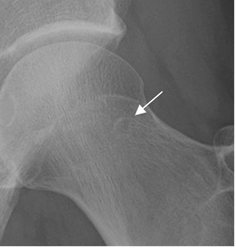

Fig 31A. Variante normal.

Rx AP. Hernia sinovial.

Fig 32. Variante normal.

Rx AP. Barra trabecular.